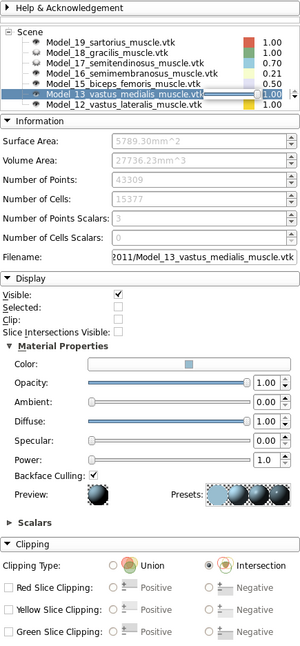

| qMRMLModelDisplayNodeWidget |

|

A widget that represents any vtkMRMLModelDisplayNode |

| qMRMLDisplayNodeWidget |

|

A widget that represents any vtkMRMLDisplayNode |

| qMRMLModelInfoWidget |

|

A widget that shows model internal data properties |

| qMRMLVolumeInfoWidget |

|

A widget that shows volume internal data properties |